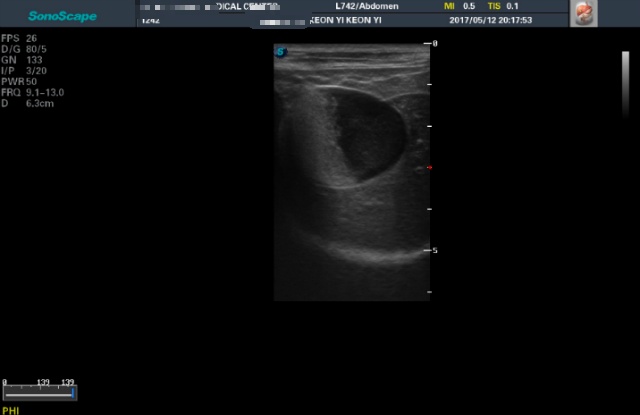

<4월25일 초진>

<5월12일 재검> 이땐 텅빈 반쪽이나마 너무 기뻤었어요...